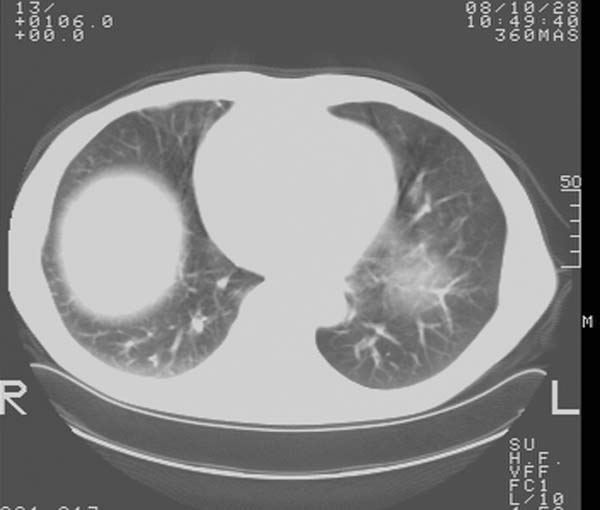

m,65y。半年前发现颈小结节,逐渐增多增大,现双侧耳后、颌下及颈部表浅淋巴肿大。胸片示双肺门增大。外院曾穿刺诊断为淋巴结核。在我科作胸腹部ct,我们觉得外院病检有误。现将图像上传请战友讨论。

纵隔内及腹膜后广泛淋巴结肿大,脾大,肝内似可见低密度影,结合病史半年前发现颈小结节,逐渐增多增大,现双侧耳后、颌下及颈部表浅淋巴肿大。考虑淋巴瘤。

纵隔,双肺门腹膜后多发淋巴结重大,非融合,肝脾轻度肿大,双肺野弥漫性小结节;考虑淋巴瘤,结节病可能性

纵隔内,双肺门、腋窝及腹膜后多发肿大淋巴结影,肺内小结节影,肝脾体积增大,支持淋巴瘤。肝内多发低密度影,考虑小囊肿。

考虑淋巴瘤肺、肝内转移,脾脏肿大。